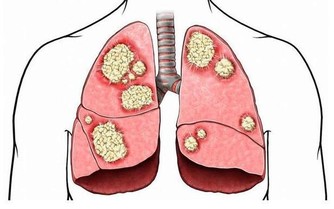

有對長壽的夫妻,丈夫不菸不酒愛運動,是個瘦子,太太則完全相反,是個胖子,兩人同時得到流感,變成肺炎!結果太太幾天就恢復出院,丈夫卻住進加護病房...為甚麼會這樣呢?醫生解釋,因為瘦,膽固醇低,罹患肺炎時,身體沒有儲備能量,容易有併發症。

圖片來源: www.haohanguo.com(圖為示意圖)